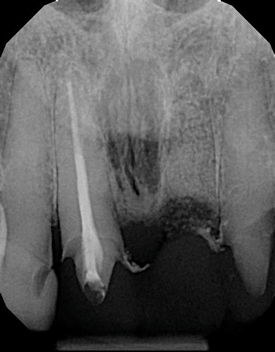

Are most or all dentists qualified to read CBCT images? Although the technology can be intimidating to clinicians who are not experienced in its use, the truth of the matter is that it is easier to identify structures and pathoses in CBCT images than in any 2D radiograph. This is made clear by the ability of patients to see and understand the images presented to them without receiving any formal training whatsoever. Because all dentists are trained in radiology, they can easily read a radiographic image created by a cone beam. The real issue for clinicians involves mastery of the software that their particular CBCT unit uses so that they can manipulate the images and best visualize the area in question.9 To this end, the education and training provided by the manufacturers of CBCT units can be very helpful to clinicians before they are able to gain experience through multiple evaluations of images (Figure 11 and Figure 12).

(11.) A pathosis apical to the maxillary central incisors was initially not diagnosed after evaluating the periapical film; however, the CBCT image revealed its presence. Only using the CBCT image could it be determined that the lesion was not odontogenic in origin and that it did not involve the nasopalatine foramen. This diagnosis was supported by a referral to an oral and maxillofacial radiologist.

Figure 11

(12.) A pathosis apical to the maxillary central incisors was initially not diagnosed after evaluating the periapical film; however, the CBCT image revealed its presence. Only using the CBCT image could it be determined that the lesion was not odontogenic in origin and that it did not involve the nasopalatine foramen. This diagnosis was supported by a referral to an oral and maxillofacial radiologist.

Figure 12